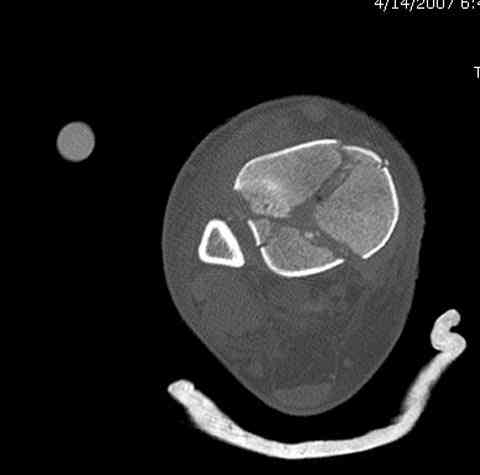

Дополнительные ренгенограммы после дистракции и

обязательная комьютерная томография дают возможности разузнать топографию расположения фрагментов, что немаловажно для планирования хирургического доступа.

По апексу фрагмента ориентируется при планировании

фиксации, также предоперационно определяется

направление фиксирующего материала: шурупа или спицы с упорной площадкой.

Переломы пилона сопровождаются ударом со сминанием в метафизарной части большеберцовой, то есть со значительной потерей костного объема.

При репозиции суставных поверхностей образуются полости в метафизарных отделах, без заполнения их

структуральными элементами невозможно предохраниться от посттравматической деформации. Латеральная колонна удерживается малоберцовой поэтому голень деформируется в варус.

Здесь выставлена пара случаев перелома пилона, оба

случая леченные этапным наружным фиксатором.